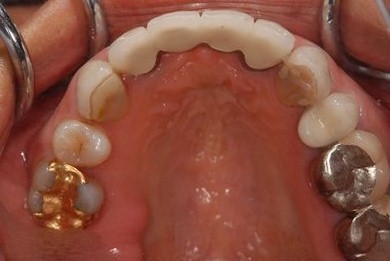

治療前

• 治療前